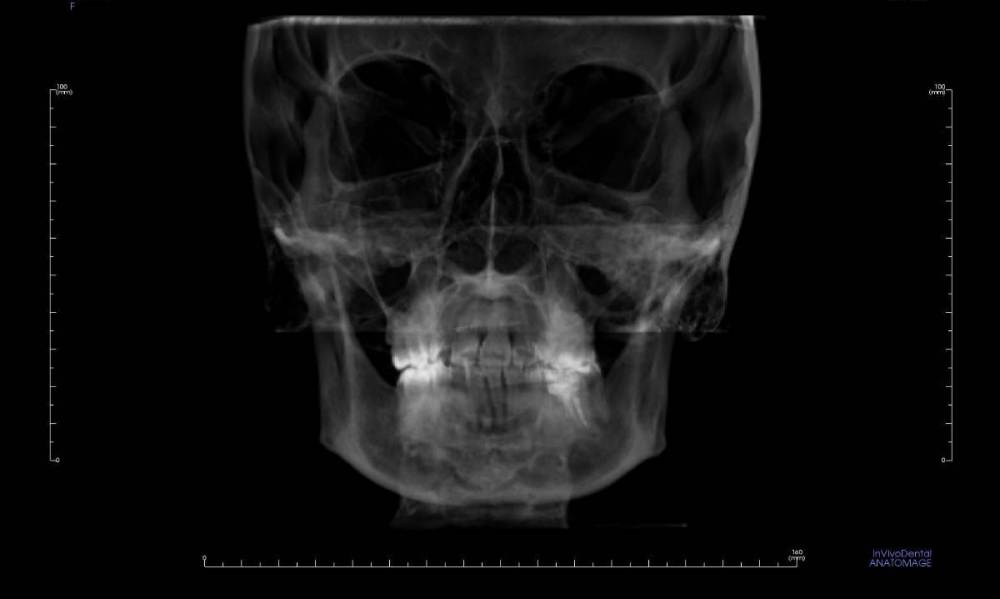

Ситуация в следующем: у меня стоят брекеты, пока только на верхней челюсти, ношу ~8 мес. На нижней челюсти в переднем отделе обнаружена цементно-костная дисплазия. Делалось два КТ, первое в 2021 (перед установкой верхней челюсти), второе месяц назад для оценки динамики перед установкой брекетов на низ. Дисплазия стала немного больше, но выглядит лучше (больше костной ткани).

Вопрос: можно ли ставить брекеты на нижнюю челюсть при таком диагнозе? Какие есть риски, осложнения? На фото КТ, сделанное в 2021